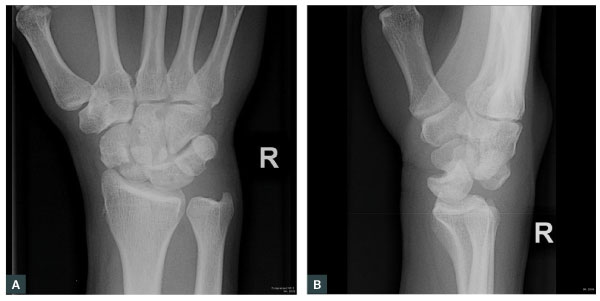

Orthopaedic surgeons need to be involved in the acute or semi-acute management of certain fractures. This includes cases where the fractures are open, displaced, neurovascularly compromised or when significant pathology is suspected. Open fractures occur when there is a fractured bone and skin break in the same limb segment.14 This increases risk for infection and non-union.32 It should be assumed that skin breaks have direct communication with the fracture, even if the open wound is not directly over the fracture.14 Initial treatment includes intravenous antibiotics, anti-tetanus toxoid if required, removal of gross contamination and covering with a simple sterile-soaked dressing and splinting/casting14 and referral for operative debridement.32 Administration of antibiotics within three hours of injury has been found to have an infection rate of 4.7%, whereas those administered after three hours had a higher infection rate of 7.4%.32 An example of a fracture with significant pathology is a trans-scaphoid perilunate dislocation with capitate lunate disruption, dorsal displacement of the capitate on the lunate, fracture through the waist of the scaphoid with a maintained radial lunate articulation (Figure 2).

Figure 2. Trans-scaphoid perilunate fracture dislocation. (A) Frontal X-ray. (B) Lateral X-ray.

Reproduced from Gaillard F. Trans-scaphoid perilunate fracture dislocation (rID: 18058). Radiopaedia.org, 2012. Available at https://radiopaedia.org/cases/trans-scaphoid-perilunate-fracture-dislocation, with permission from Radiopaedia.org.43

R, right.